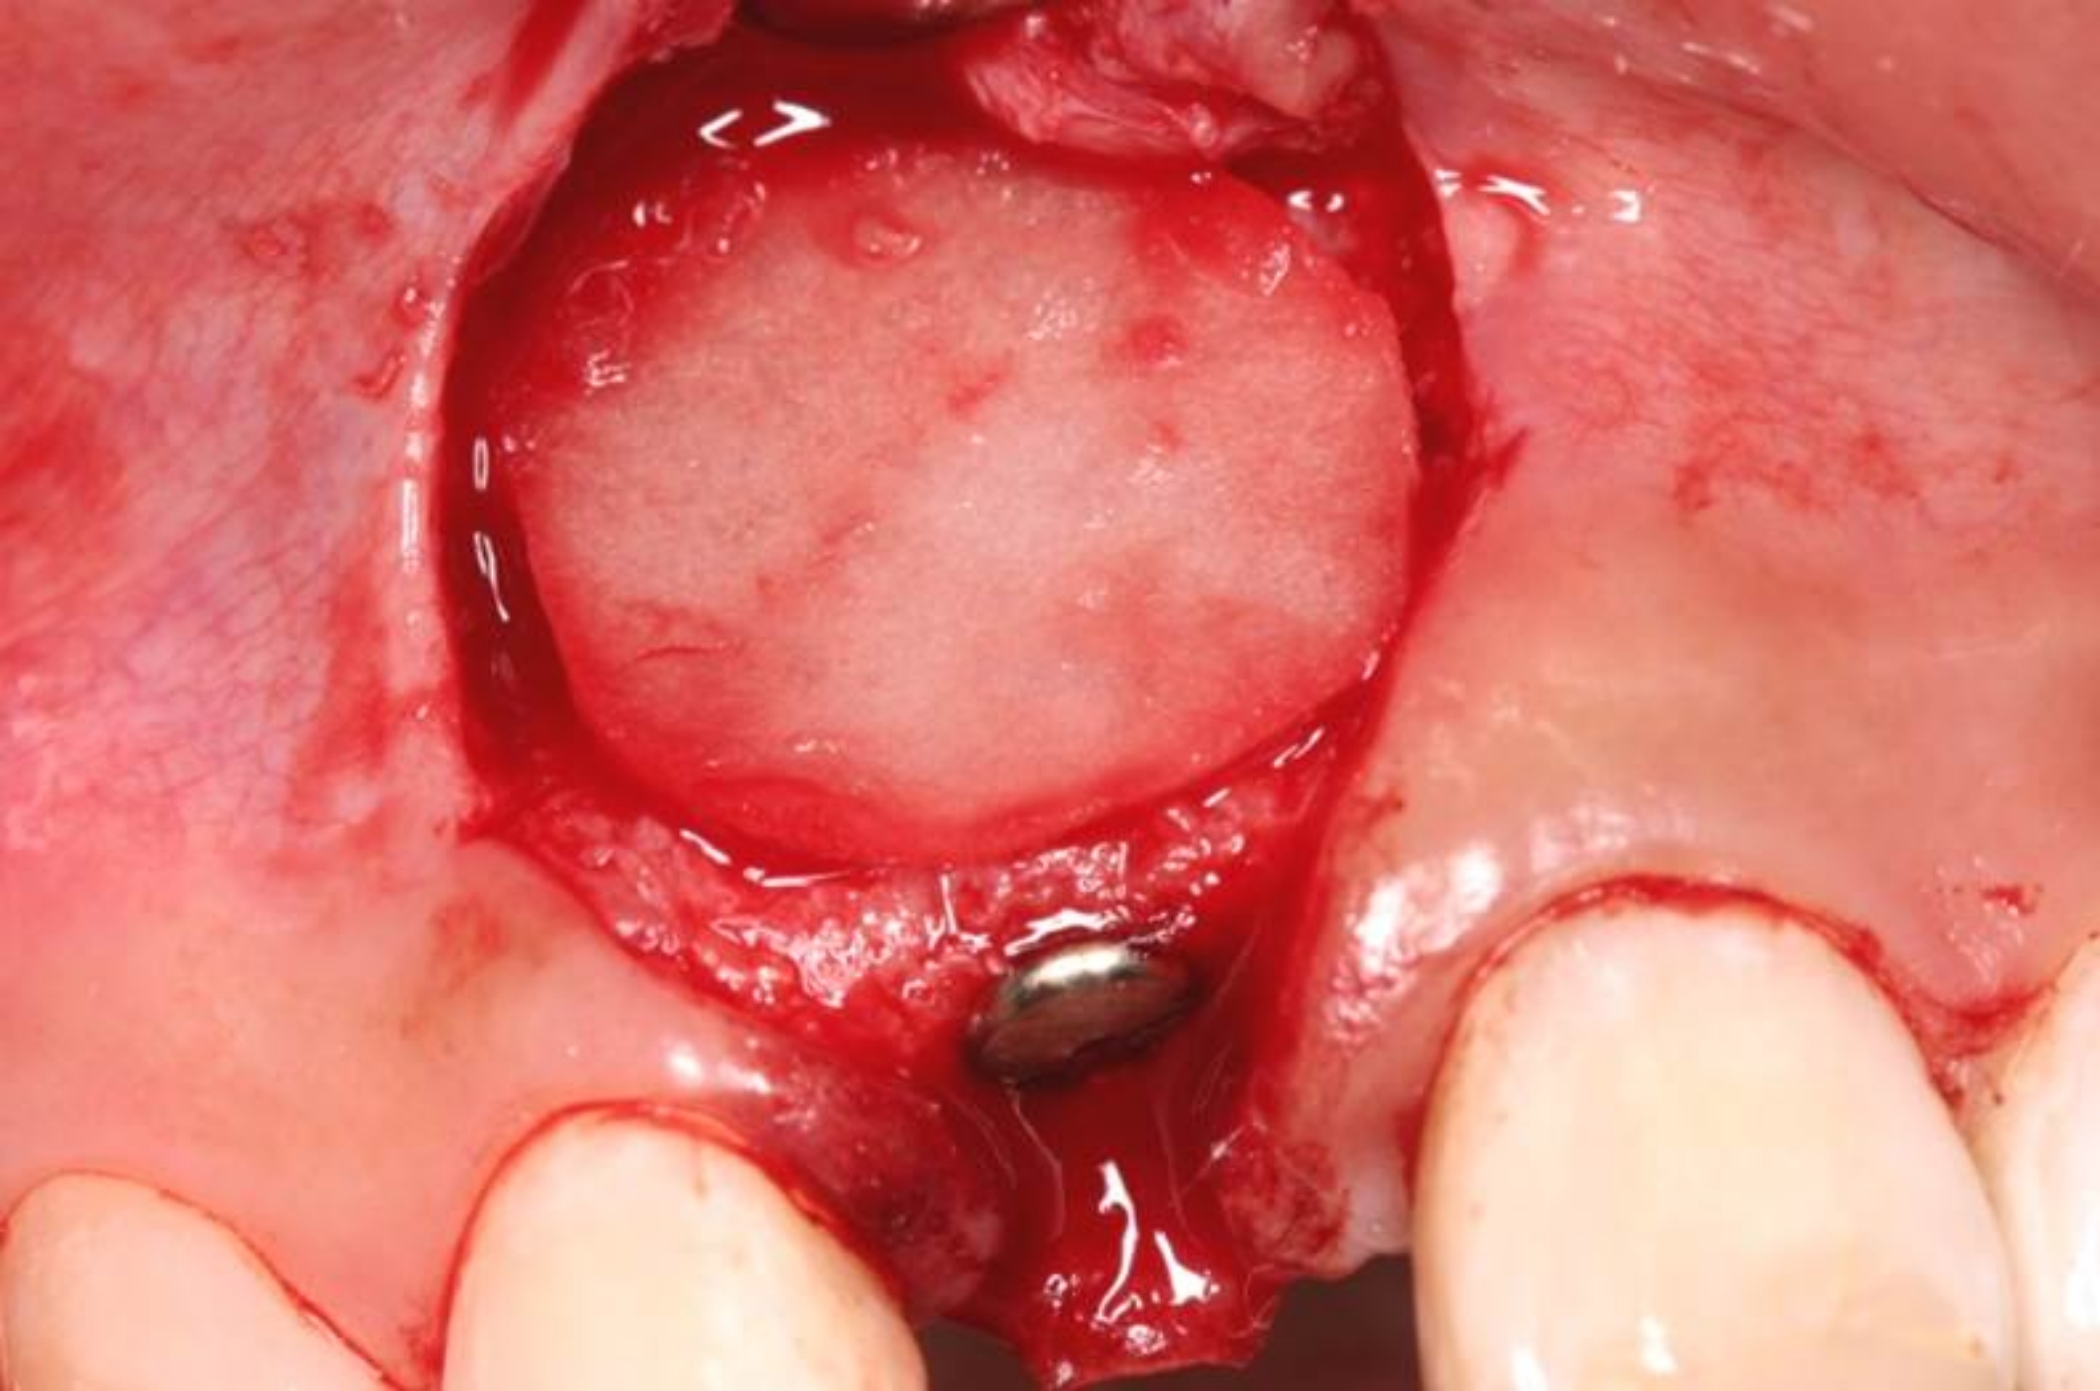

Fig 1. Case 1: A horizontal releasing incision across the edentate ridge at the site of tooth No. 8. It terminates 1 mm from the adjacent teeth.

Figure 1